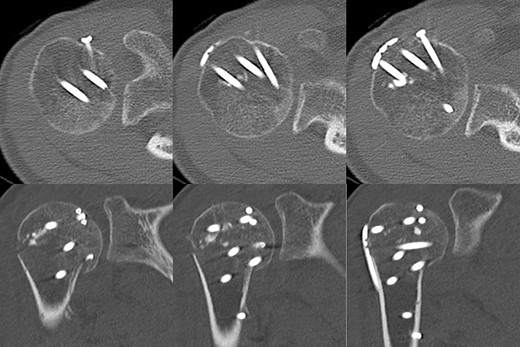

Postoperative radiographic and CT evaluations showed reduced fractures on the humeral head and surgical neck (Fig. 7). At 24 months of postoperative follow-up, radiographic and CT evaluations showed no signs of osteoarthritis or reimpression (Fig. 8). Two years after the primary surgery, we performed implant removal at the patient’s request (Fig. 9). When performing implant removal, we additionally performed a second-look evaluation with arthroscopy to assess the degree of healing in the joint. We noted no impression or exposure of cartilage callus on either side of the humeral head or glenoid (Fig. 10).

Postoperative X-ray and CT scan showing sustained anatomical reconstruction of articular surfaces and no signs of osteoarthritis.

Two years later, pre-implant removal CT showed that the reduction in the depressed surface had been maintained with no obvious arthritic changes.